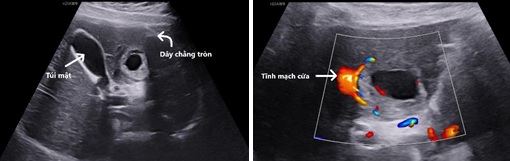

Hình 1, 2: Túi thai nằm ở hạ phân thùy IVb gan trái, giữa dây chằng tròn và túi mật. Tăng sinh mạch máu quanh túi thai, túi thai nằm rất sát một nhánh của tĩnh mạch cửa trái.

+ Ngã bụng: Gan trái ở hạ phân thùy IVb có một cấu trúc giống túi thai bờ dày kích thước 25 x 27 x 33 mm, bờ ngoài không đều, trung tâm có vùng hồi âm trống. Có tăng sinh mạch máu xung quanh túi thai dạng vòng lửa. Không quan sát thấy dịch tự do ổ bụng.

Siêu âm ổ bụng: hình ảnh một túi thai có yolk sac hoặc phôi thai nằm trên bề mặt của gan có giá trị chẩn đoán cao. Hình ảnh siêu âm thường gặp là một khối hồi âm hỗn hợp với 1 khoảng hồi âm trống bên trong, với bờ ngoài không rõ và tăng sinh mạch máu xung quanh dạng vòng lửa.